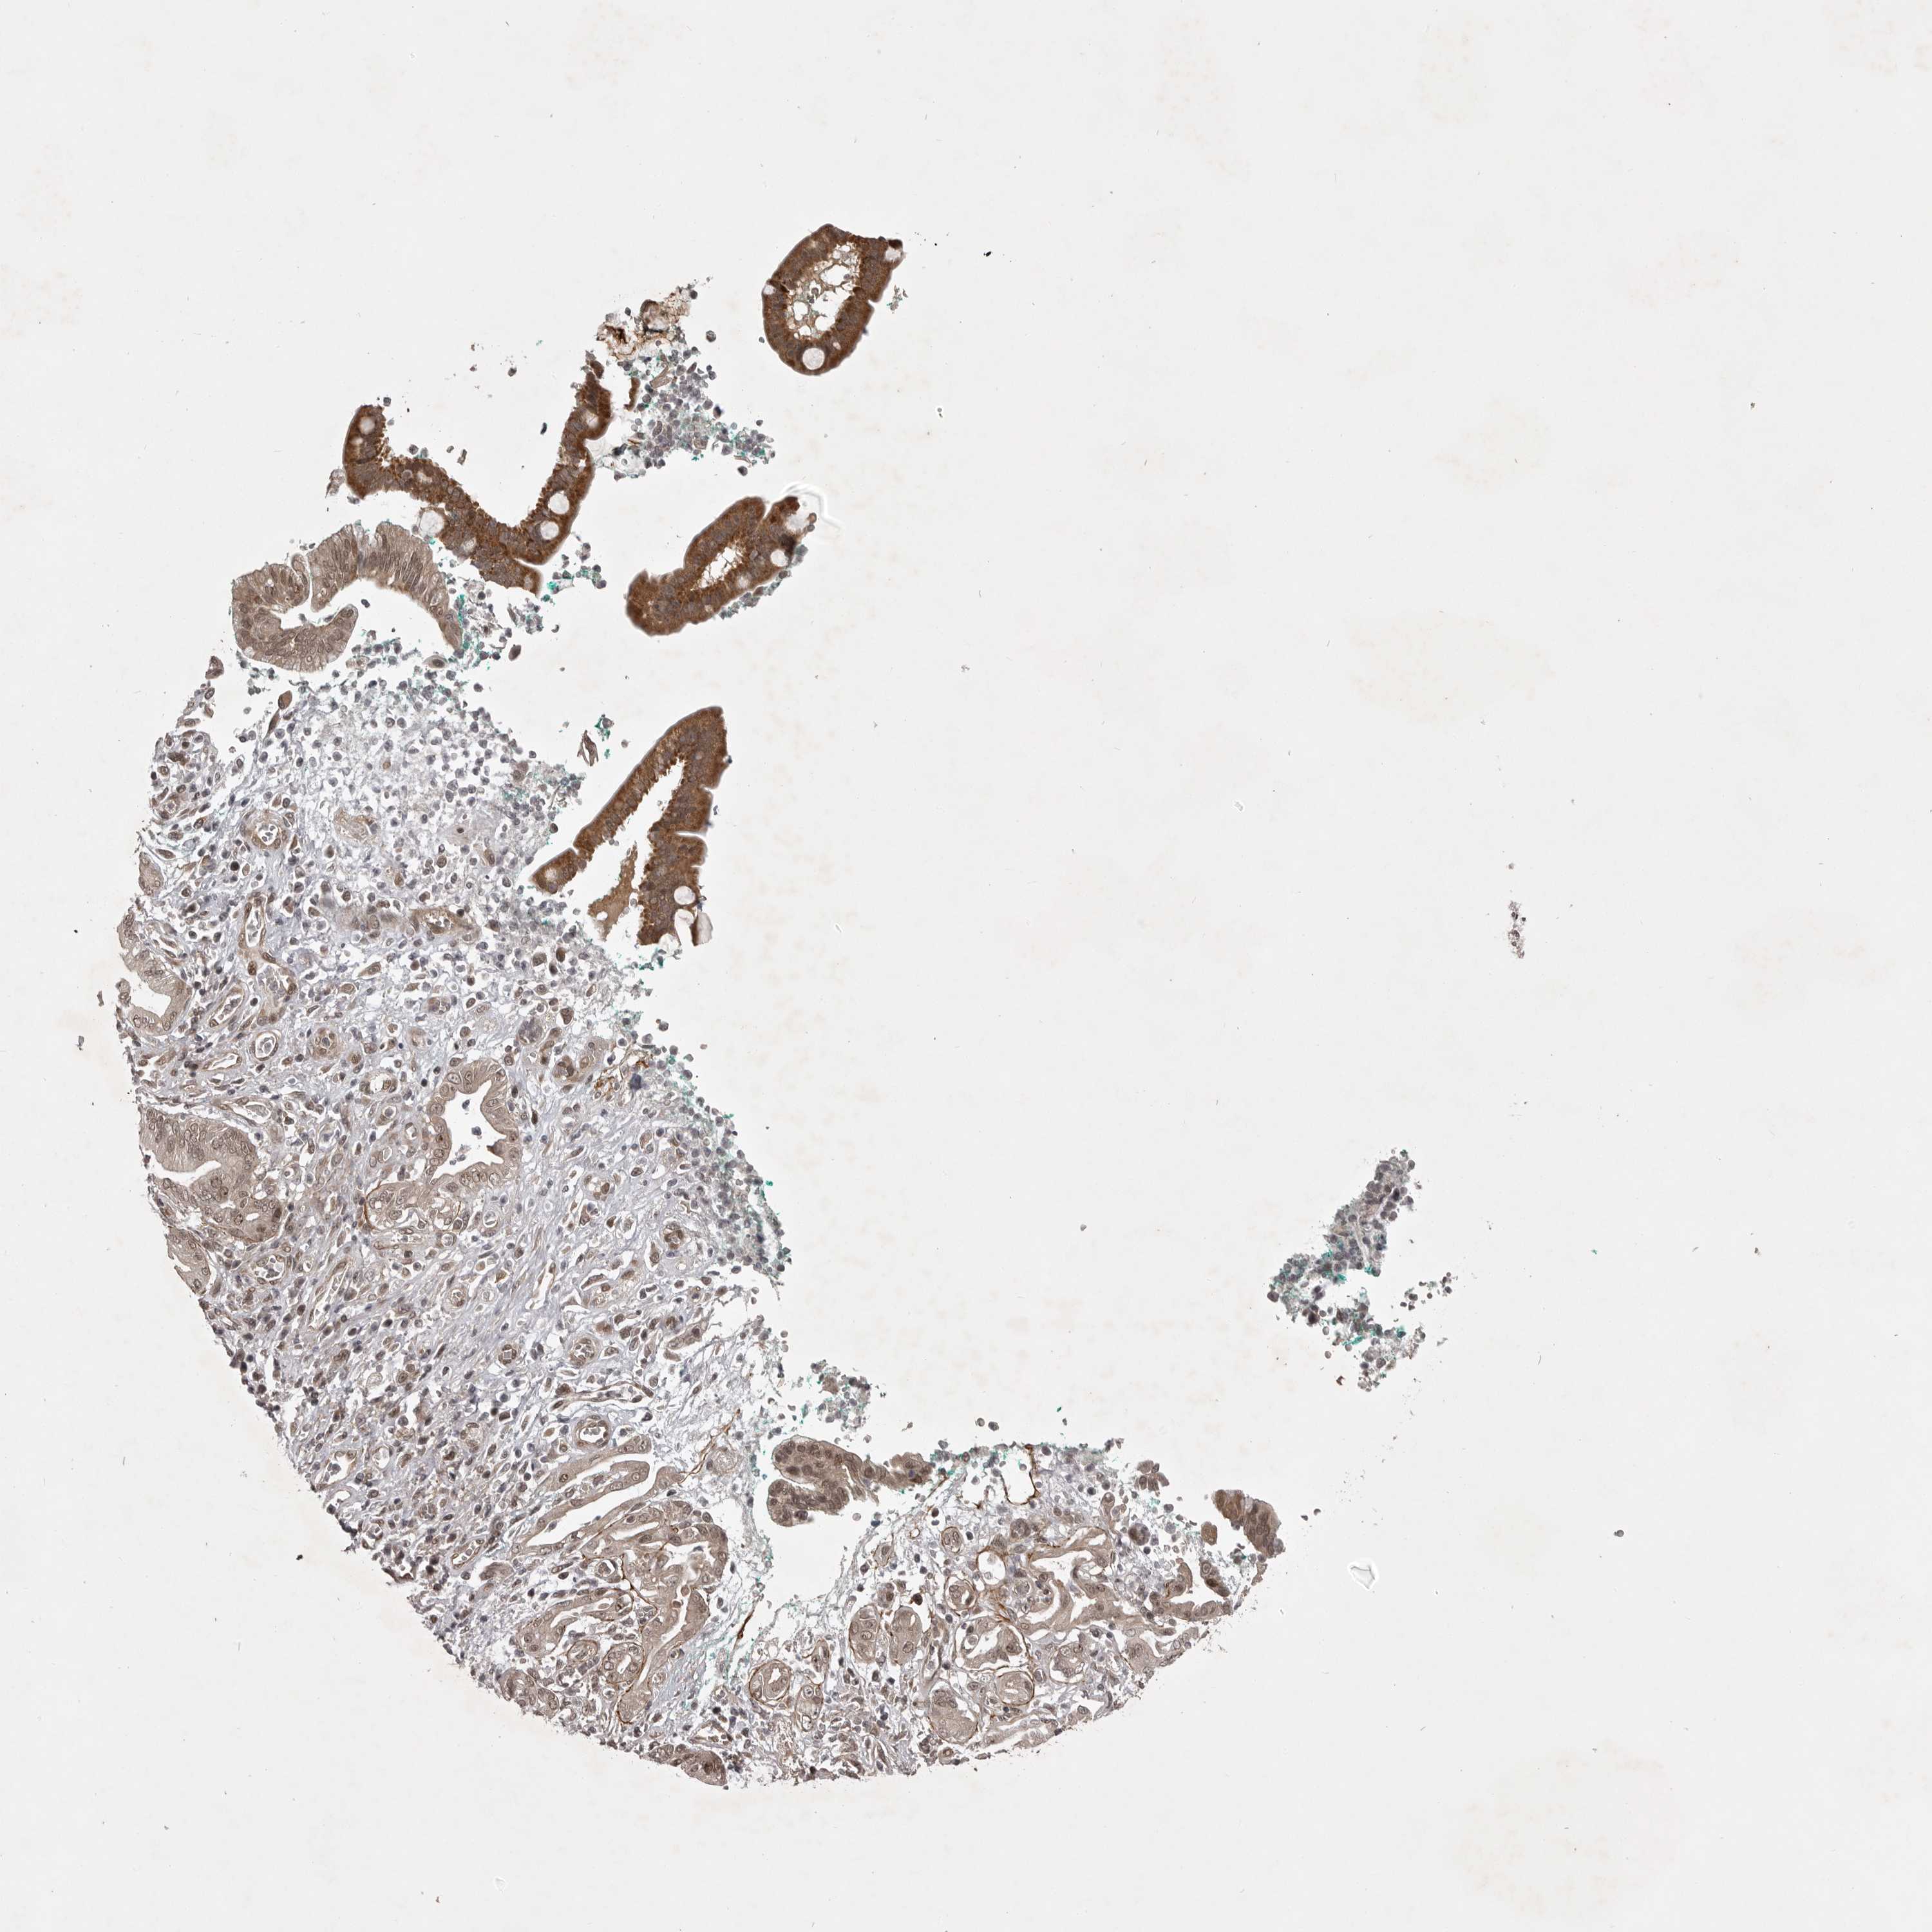

PANCREATIC CANCER - Protein expressioni

A mouse-over function shows sample information and annotation data. Click on an image to view it in a full screen mode. Samples can be filtered based on level of antibody staining by selecting one or several of the following categories: high, medium, low and not detected. The assay and annotation is described here.

Antibody stainingi

Antibody staining in the annotated cell types in the current human tissue is reported as not detected, low, medium, or high, based on conventional immunohistochemistry profiling in selected tissues. This score is based on the combination of the staining intensity and fraction of stained cells.

Each image is clickable and will lead to virtual microscopy that enables deeper exploration of all samples and also displays staining intensity scores, fraction scores and subcellular localization as well as patient and tissue information for each sample.

Antibody HPA024730

Antibody HPA024731

Antibody HPA024817

Adenocarcinoma, NOS